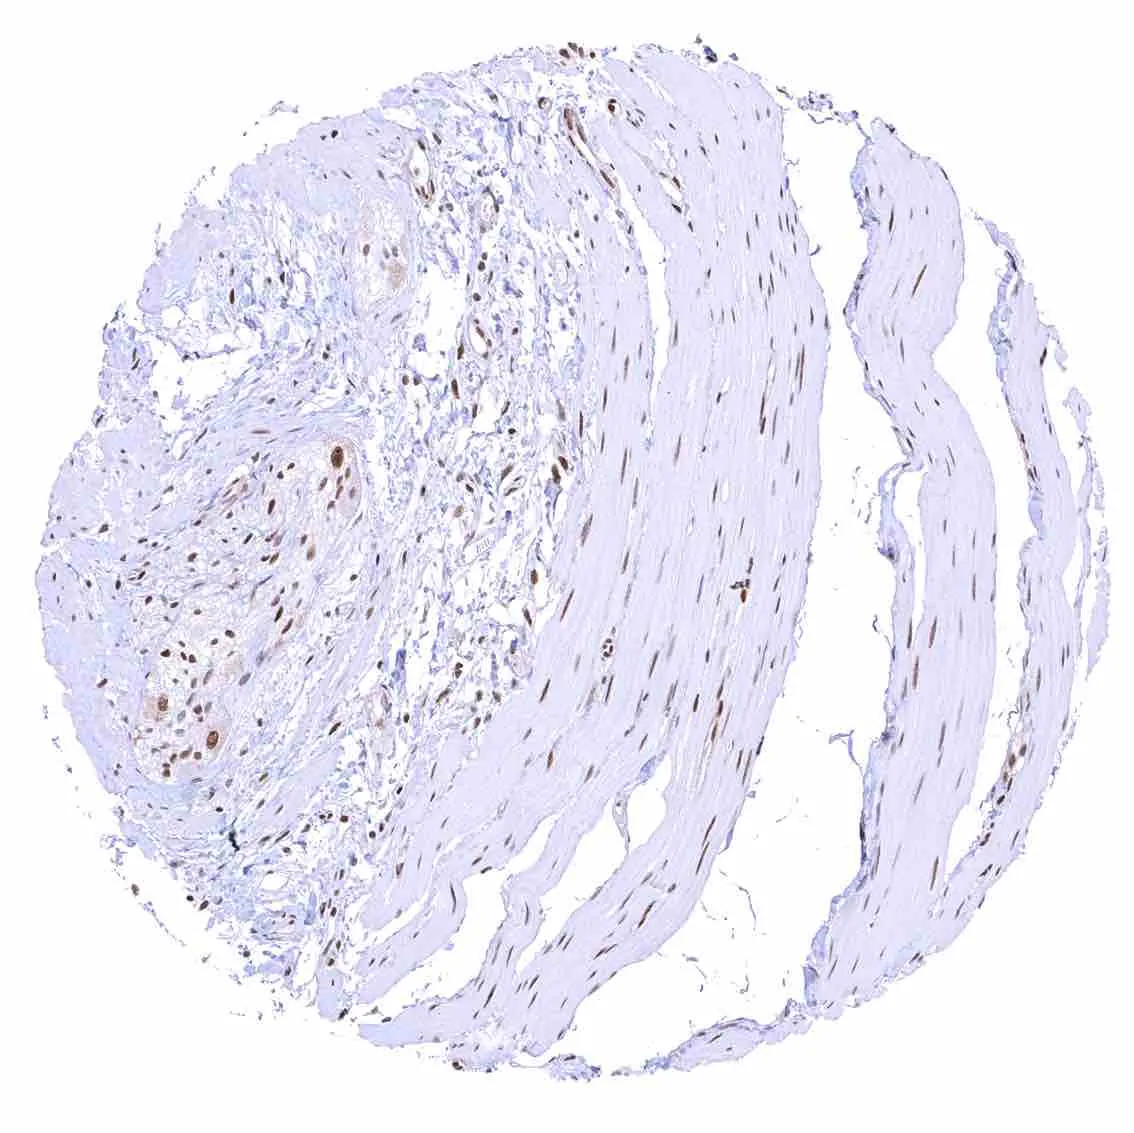

Colon descendens, muscular wall – Strong nuclear p27 staining of most smooth muscle and neuronal cells.